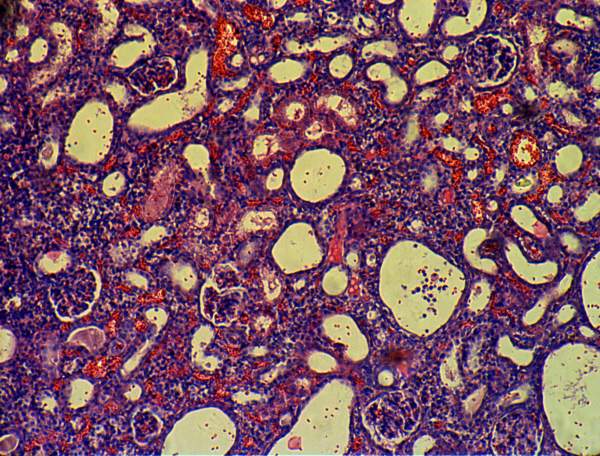

间质性肾炎切片观察